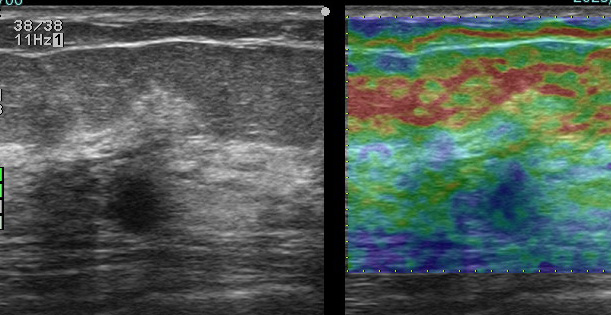

これも検診時の画像

左はエラストグラフィー(硬さを見ています 赤:柔らかい 青:硬い)

皮下脂肪は赤で柔らかく

腫瘍(中心:青)は周囲の乳腺(緑)よりも硬いことがわかります。